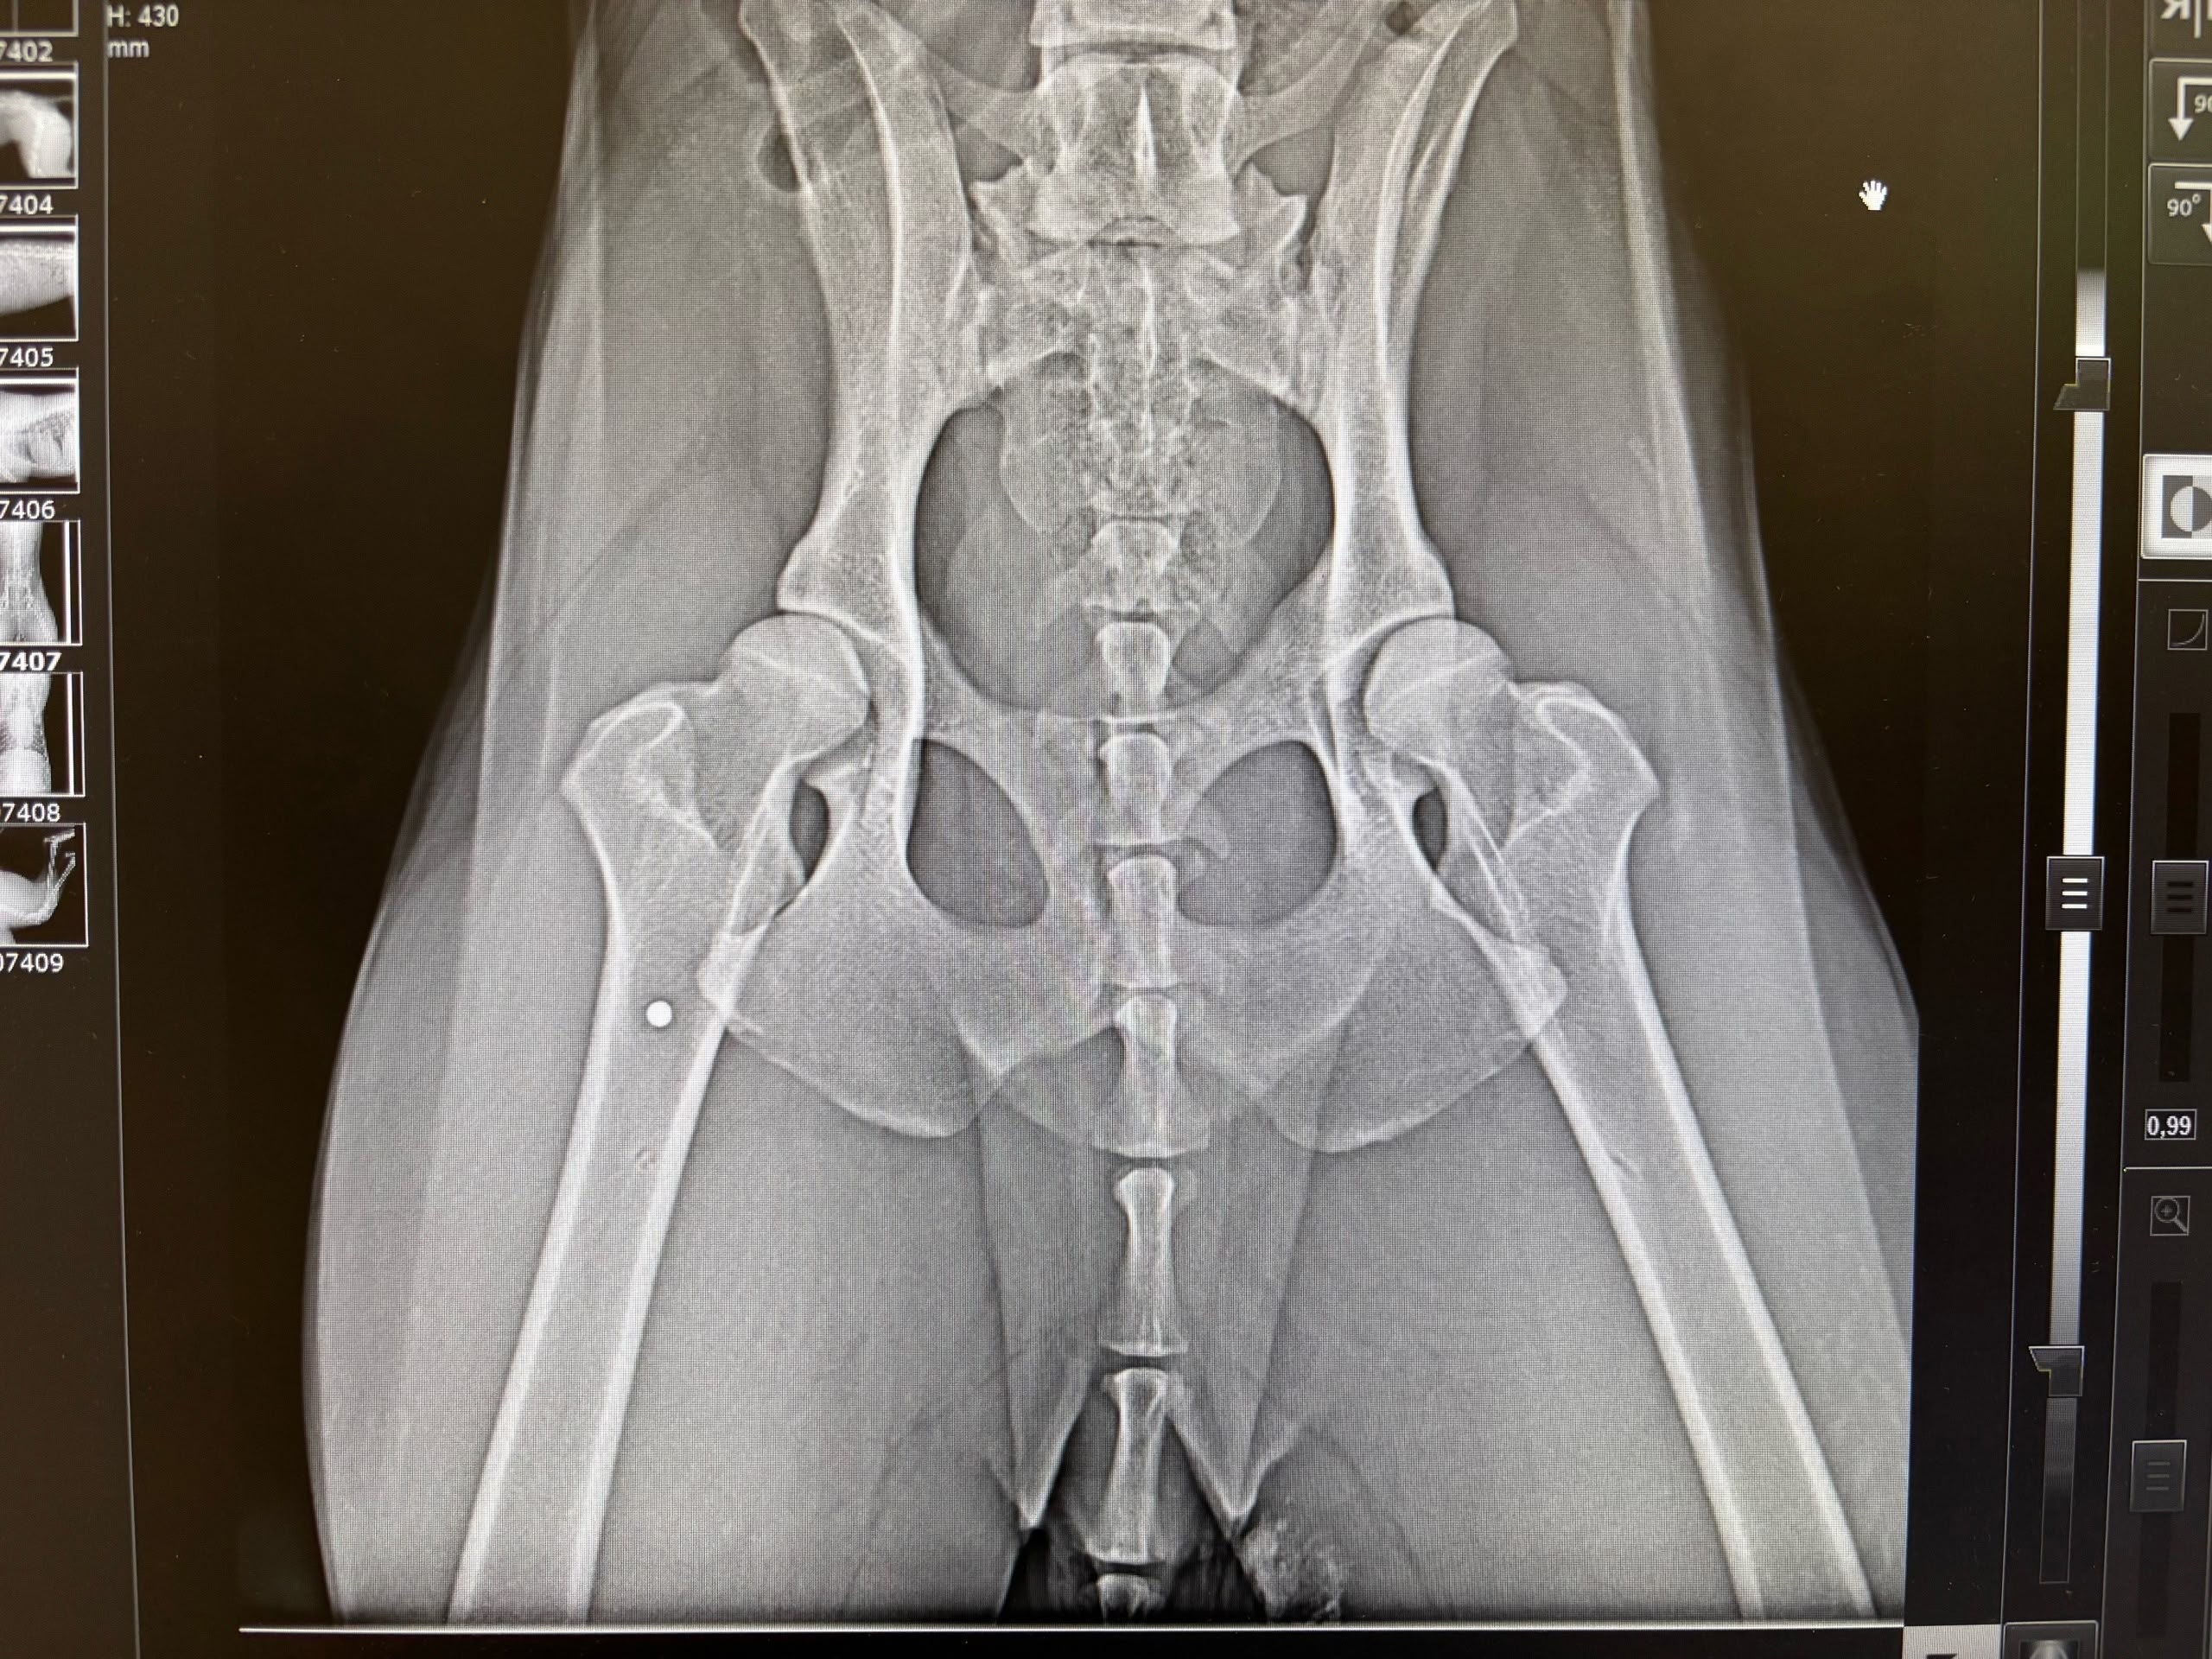

Мужчина по имени Вадим рассказал 78.ru, что отвел своих собак домой, а затем вернулся и при помощи шлейки кое-как вытащил пса, а затем передал волонтерам. Те отвезли его в выборгскую ветклинику, где рентген показал наличие дроби в позвоночнике и мягких тканях.

Позже Вадим нашел еще одну простреленную собаку, сучку, в поле и на этот раз сам отвез ее ветеринарам. И вновь на снимке медики увидели дробь.